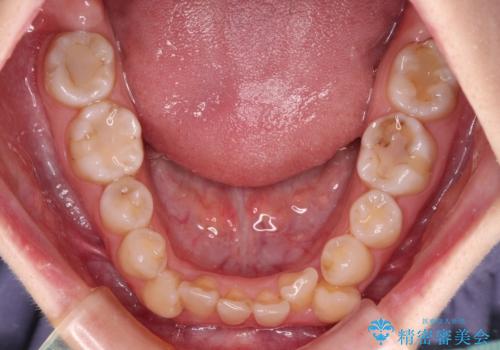

- 上下の八重歯と前歯のデコボコを気にして来院された患者様です。

右上と左下の八重歯が特に著しく、上顎正中が右側にシフトしていました。

デコボコが強いため小臼歯4本を抜歯し、上顎正中を左側に移動させるために補助装置を使用して、ワイヤー装置にて矯正治療を行うこととしました。